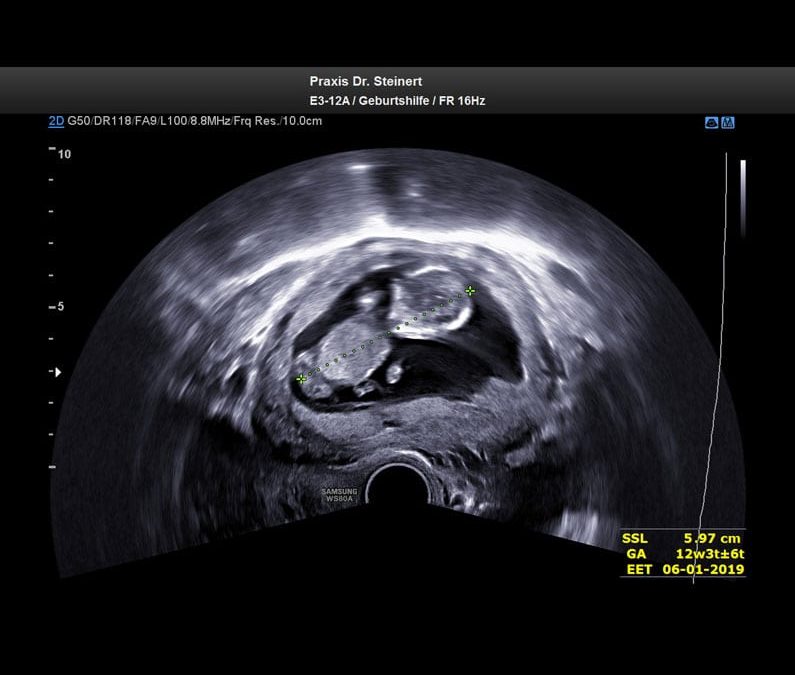

ultraschall-bild7-fruehschwangerschaft